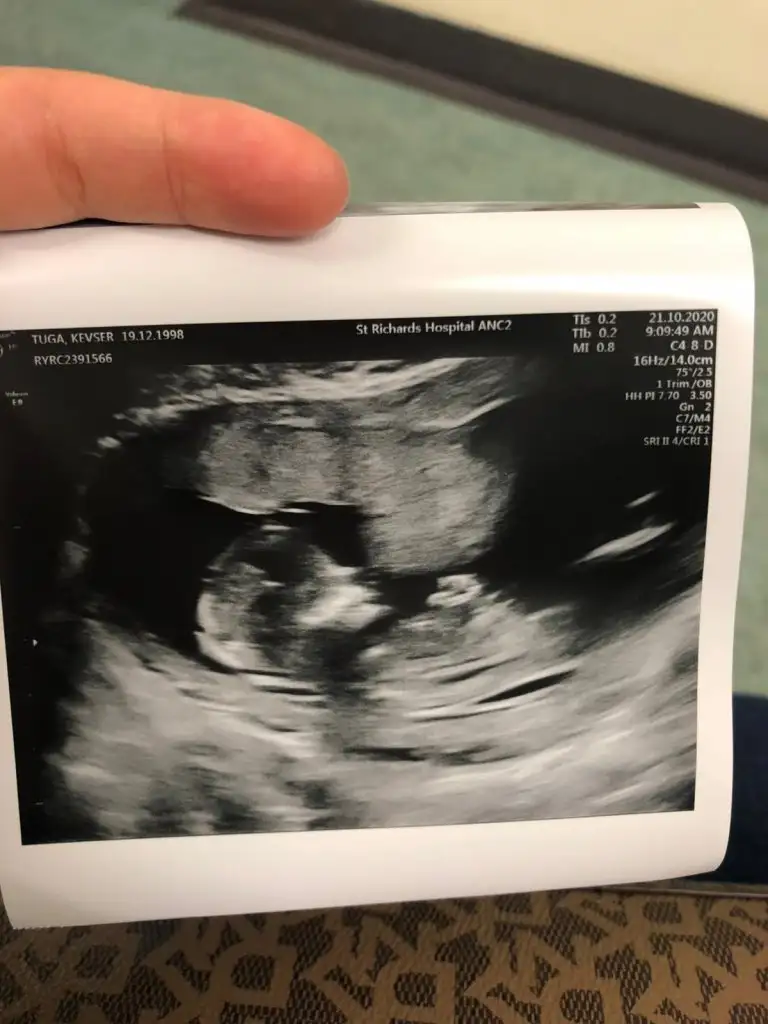

Ayy çok teşekkürler. vajinaldiii. Kalp atışı çok fazla olduğu için doktor da kız olabilir dedi. Hadi bakalım